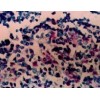

酶免疫测定

酶免疫测定(enzyme immunoassay)可分为均相(homogenous)和非均相

(heterogenous)两种类型。在均相EIA中可不需进行游离的和结合的标记物的分离而

直接测定标记物。例如在某种条件下,抗原抗体反应后形成的酶标记抗原抗体复合物中

的酶失去其对底物作用的活力,因而测出的酶活力直接反映游离的酶标记物。均相EIA在

临床检验中较少应用。非均相EIA需行游离的和结合的标记物的分离。如前所述,固

相载体可用作一种分离手段。这种固相酶免疫测定方法在1971年初建立时称为酶联免

疫吸附剂测定(enzyme linked immunosorbent assay),简称ELISA,在有译作酶

联免疫吸附试验的,虽然含义不完全确切,但已习用。